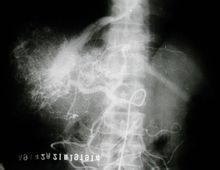

兩大血管通往肝臟:肝動脈和門靜脈。肝動脈來自腹腔乾。門靜脈引來消化道的靜脈血,肝臟就可以處理其中的營養物質和毒素。肝靜脈直接注入下腔靜脈。

微膽管(bile capillaries)收集膽汁(bile)聚集成膽道(bile duct)。接著由左、右肝管(left, right hepatic duct)回收到總肝管(common hepatic duct)。膽囊管和總肝管聚集合成總膽管(common bile duct)。總膽管在進入十二指腸前的壺腹部位(ampulla)和胰管相連線,將肝臟分泌儲存於膽囊內的膽汁直接的注入降十二指腸(descending duodenum)內幫助脂肪的代謝消化。

肝的上面隆凸稱隔面,朝向前上方,與脆彎窿相適應,能隨呼吸運動而上下移動。隔面借鐮狀韌帶將肝臟分為左右兩部,即左葉和右葉。右葉大而厚;左葉小而薄。肝的下面凹凸不平,稱為髒面,朝向後下方,與腹腔器官相鄰。髒面的中部有H形的兩條縱溝和一條橫溝。左側縱溝的前部有肝圓韌帶,為胚胎時期的臍靜脈閉鎖的遺蹟;右側縱溝的前部容納膽囊,後部緊接下腔靜脈。橫溝叫肝門肝固有動脈、門靜脈、肝管、淋巴管及神經等由此進入肝臟。

肝臟呈一不規則楔形,右側鈍厚而左側扁窄,藉助韌帶和腹腔內壓力固定於上腹部,其大部分位於右側季肋部,僅小部分超越前正中線達左季肋部。外觀可分膈、髒兩面,膈面光滑隆凸,大部分與橫膈相貼附,其前上面有鐮狀韌帶,前下緣於臍切跡處有肝圓韌帶;鐮狀韌帶向後上方延伸並向左、右伸展稱冠狀韌帶,冠狀韌帶又向左、右伸展形成左、右三角韌帶,在右冠狀韌帶前後葉之間,有一部分肝面沒有腹膜復蓋,稱肝裸區。髒面有兩個縱溝和一個橫溝,構成H形。右縱溝由膽囊窩和腔靜脈窩組成,其後上端為肝靜脈進入下腔靜脈處,即第2肝門所在,其後下端為肝短靜脈匯入下腔靜脈處,此為第3肝門所在;左縱溝則由臍靜脈窩和靜脈韌帶組成;橫溝連線兩縱溝,為第1肝門所在,在橫溝右端伸向肝右方,常見一側溝,稱右切跡。